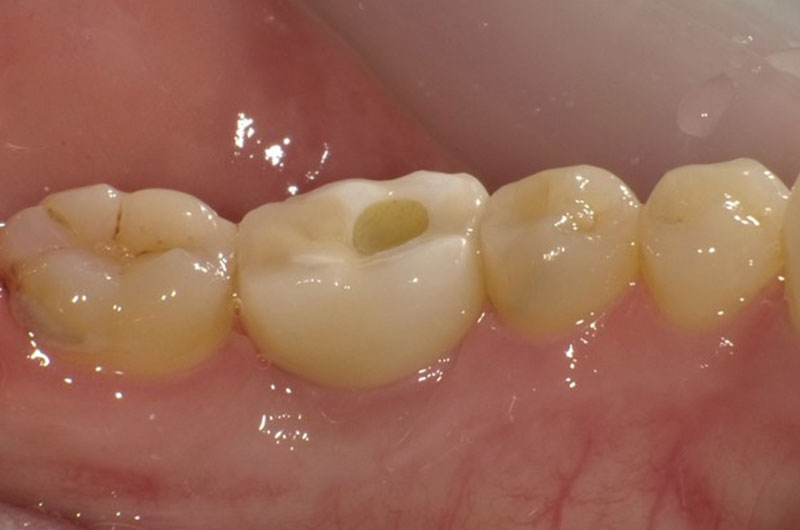

| 治療ケース | 下顎:右下7 抜歯後、骨造成(GBR)を行い 静脈内鎮静・局所麻酔を行い、1本のインプラントを埋入(1回法)。3か月後にプロビショナル装着。5ケ月後に上部構造オールセラミック装着。 |

| 症状 | 右下7の歯根の周りが膿んでいる。 |

| 治療結果 | 歯根の周囲が広範囲に膿んでいて抜歯が必要な状態。抜歯後、骨造成(GBR)を行い待機後、1次オペ。骨質も良く良好な初期固定が得られ1次手術、2次手術を同時に行う1回法で手術を行えました、経過も良好でしっかり咬めるようになったと大変満足されています。 |

| 治療開始月 | 2017年6月 |

| 治療期間 | 約10ヶ月 |

| メインテナンスの頻度 | 3ケ月毎 |